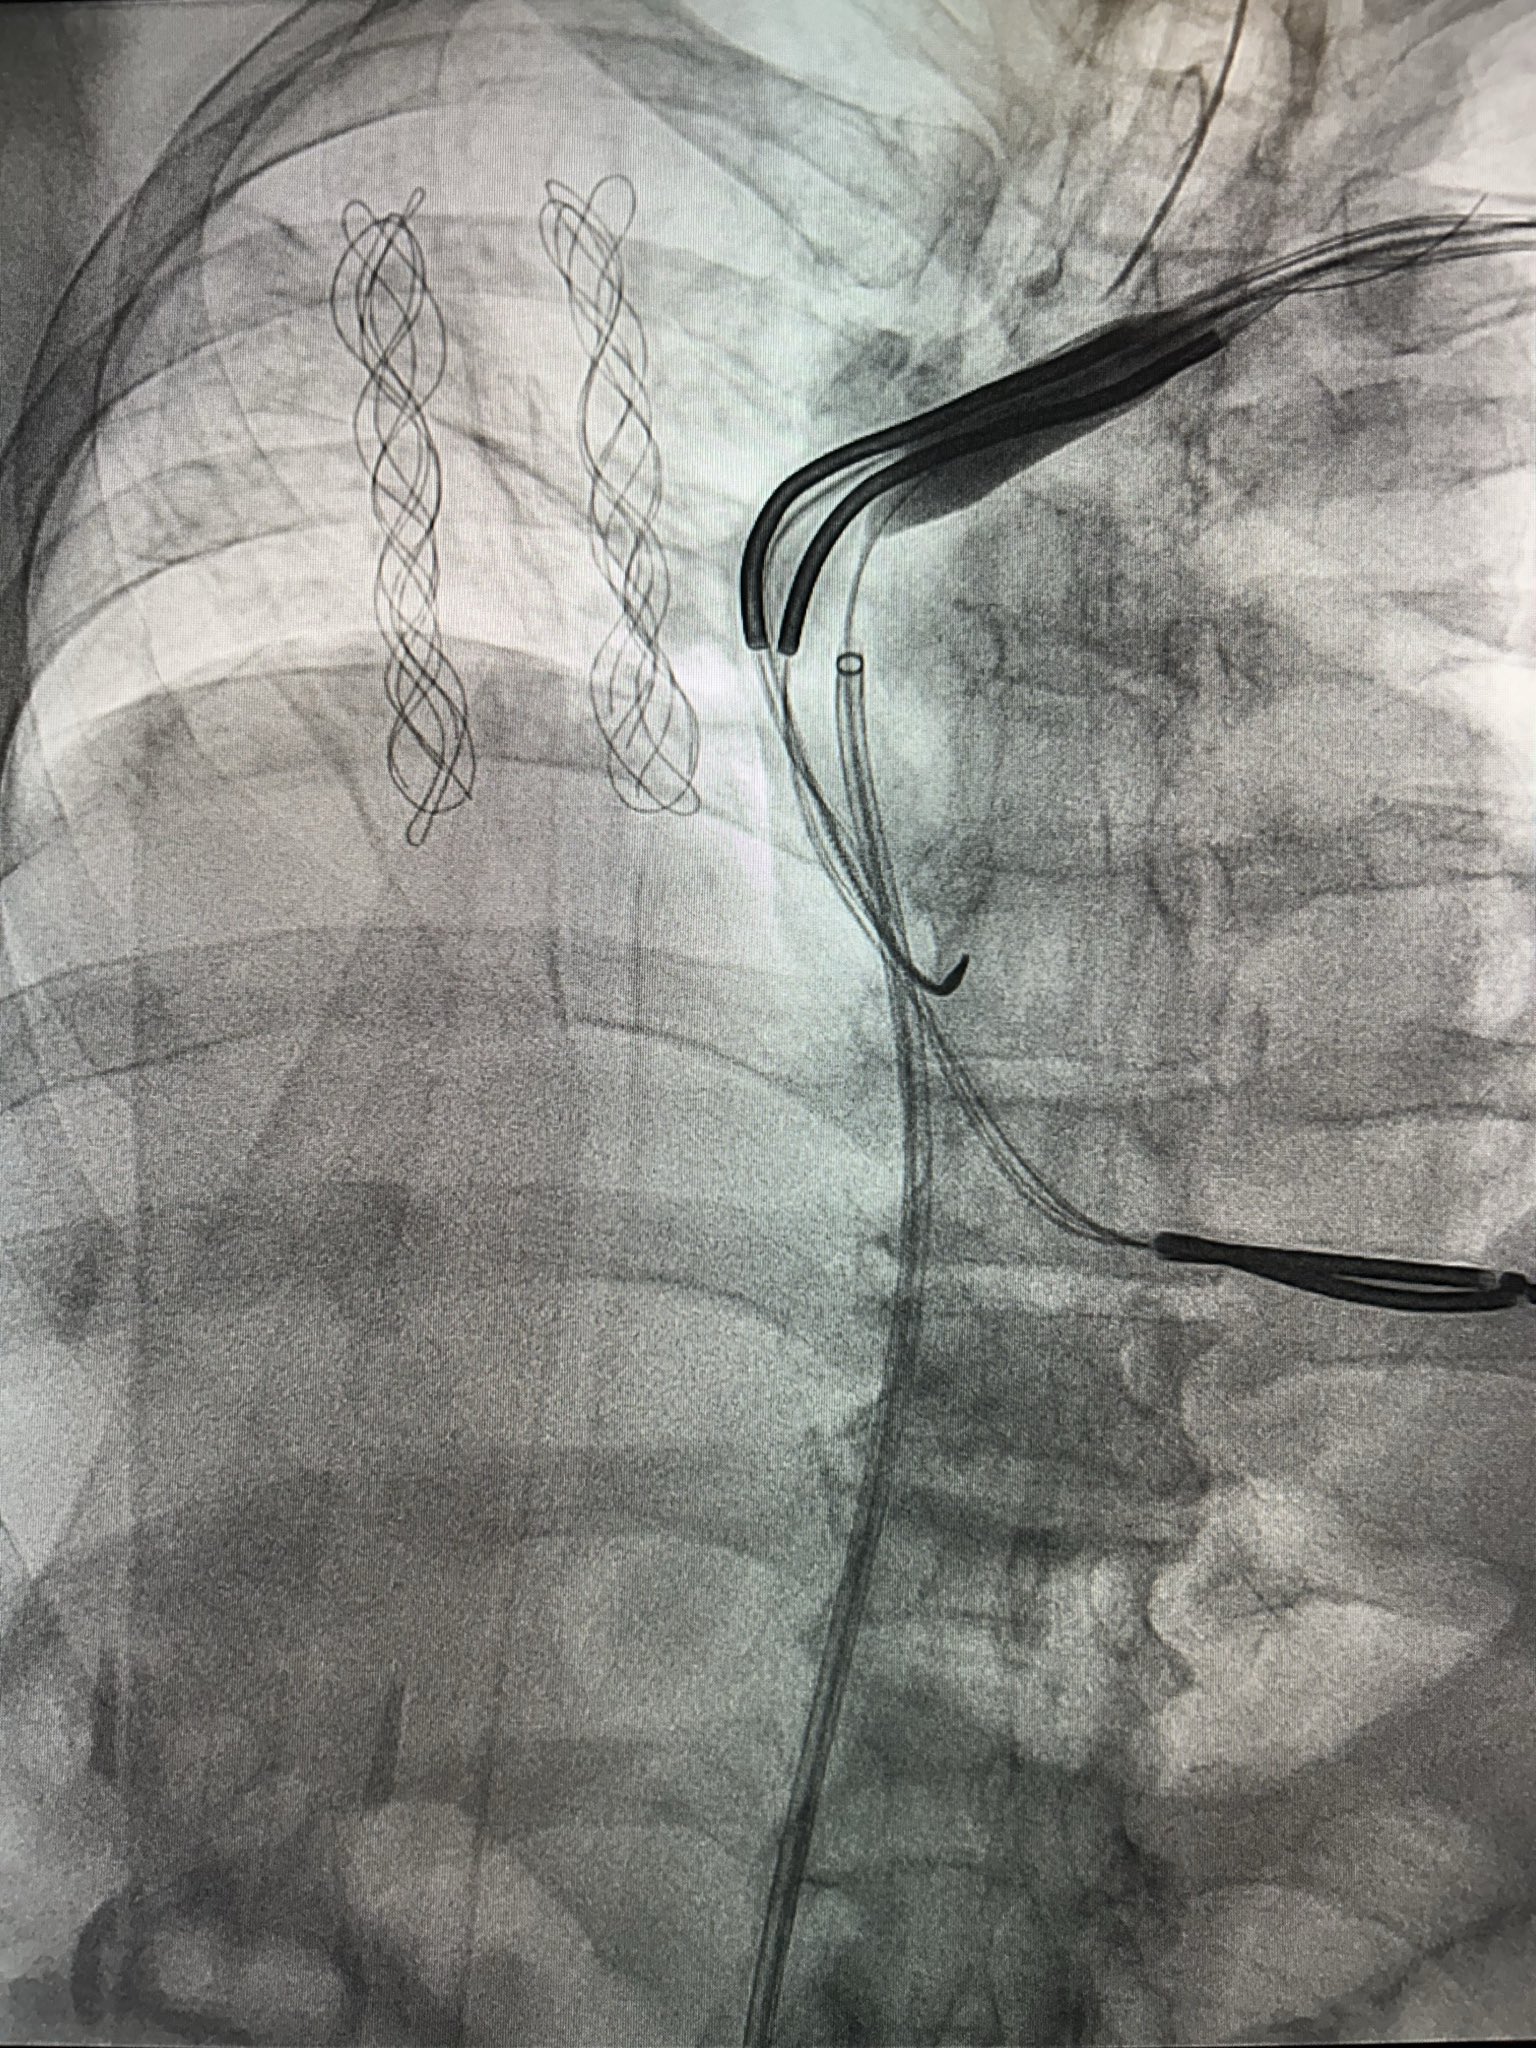

Patient with an abandoned 16 year old dual coil ICD lead, RA lead fracture, and generator at ERI.

Shockwave with a 12mm balloon to the axillary, subclavian, and SVC.

Extracted both leads with 16Fr laser and preserved existing ICD lead.

#Epeeps #extraction #shockwave